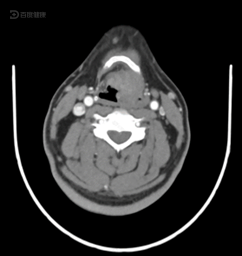

跨声门癌 喉癌同时侵犯声 门上中下区,粘 膜下生长,喉镜 检查常阴性

声门型喉癌的ct分析